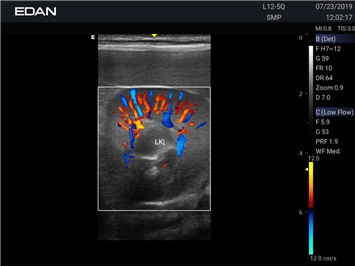

EDAN Acclarix AX2 VET

Ветеринарный ультразвук одним нажатием. Система Acclarix AX2 VET разработана с целью обеспечить бескомпромиссную производительность по доступной цене. Наличие уникальных двойных аккумуляторов в легком корпусе массой 4,5 кг из магниевого сплава позволяет системе Acclarix AX2 VET удовлетворять все потребности ветеринарных исследований, сохранив низкую стоимость.

EDAN Acclarix AX2 VET представляет собой специализированную ветеринарную ультразвуковую систему, сочетающую высокую производительность с доступной ценой. Благодаря продуманной конструкции и передовым технологиям, система обеспечивает качественную диагностику животных различных видов.